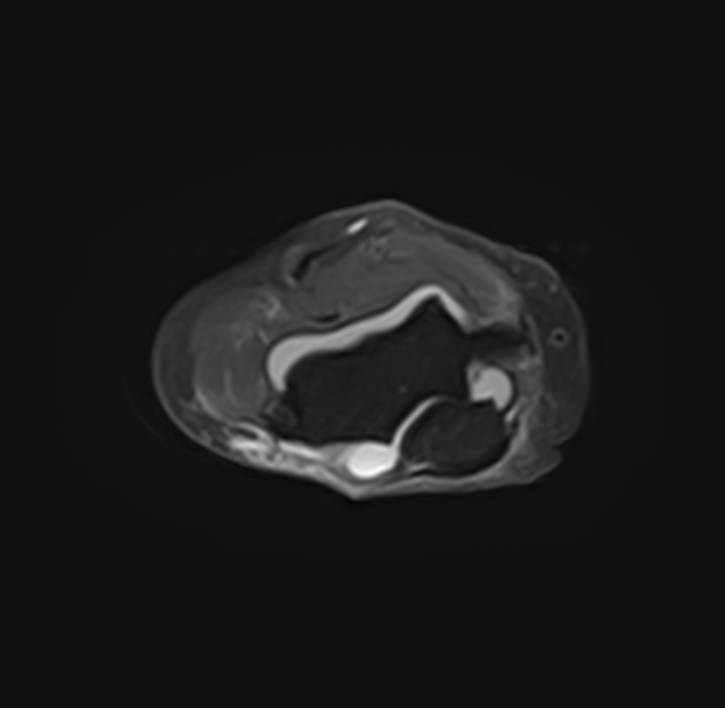

Локтевой сустав представляет собой подвижное сочленение плечевой кости с лучевой и локтевой костями предплечья. Сочленение имеет сложное строение и состоит из трех суставов, заключенных в одной составной капсуле. Сустав выполняет несколько видов движений и испытывает интенсивные нагрузки, поэтому часто подвергается травматизации и развитию различных заболеваний, в том числе, воспалительных и дегенеративно-дистрофических. Болевой синдром в локтевом суставе, который возникает при многих патологиях, требует проведения дифференциальной диагностики с помощью высокоточных методов обследования.

Магнитно-резонансная томография является наиболее информативным методом диагностической визуализации всех структур локтевого сустава, включая костные структуры, связки, сухожилия, прилегающие мягкие ткани. По сравнению с другими методами обследования, такими как УЗИ, рентгенография и компьютерная томография, МРТ позволяет получить наибольшую информацию о патологических процессах в суставе и окружающих тканях, поставить точный диагноз и определить тактику лечения. При этом МР томография не оказывает вредного воздействия на организм, так как технология процесса не предусматривает использование рентгеновского излучения.

В клинике «Доступная медицина» проводится МРТ локтевого сустава на современном томографе закрытого типа TOSHIBA VANTAGE TITAN 1,5 Тесла. Благодаря высокой мощности магнитного поля устройство при сканировании выявляет даже минимальные очаги поражения сустава и на основе полученных данных проводит построение 3D-модели. Кроме того, для увеличения информативности МРТ в некоторых случаях применяется введение контрастного вещества, содержащего в своем составе металл гадолиний.

Что показывает МРТ локтевого сустава

При глубинном и тщательном исследовании, МРТ обеспечивает легкое обнаружение ряда проблем, которые достаточно сложно диагностировать визуально, посредством анализов или других методик диагностики. Иногда это сделать вовсе невозможно. Без оперативного вмешательства, с помощью МРТ локтевого сустава можно определить: